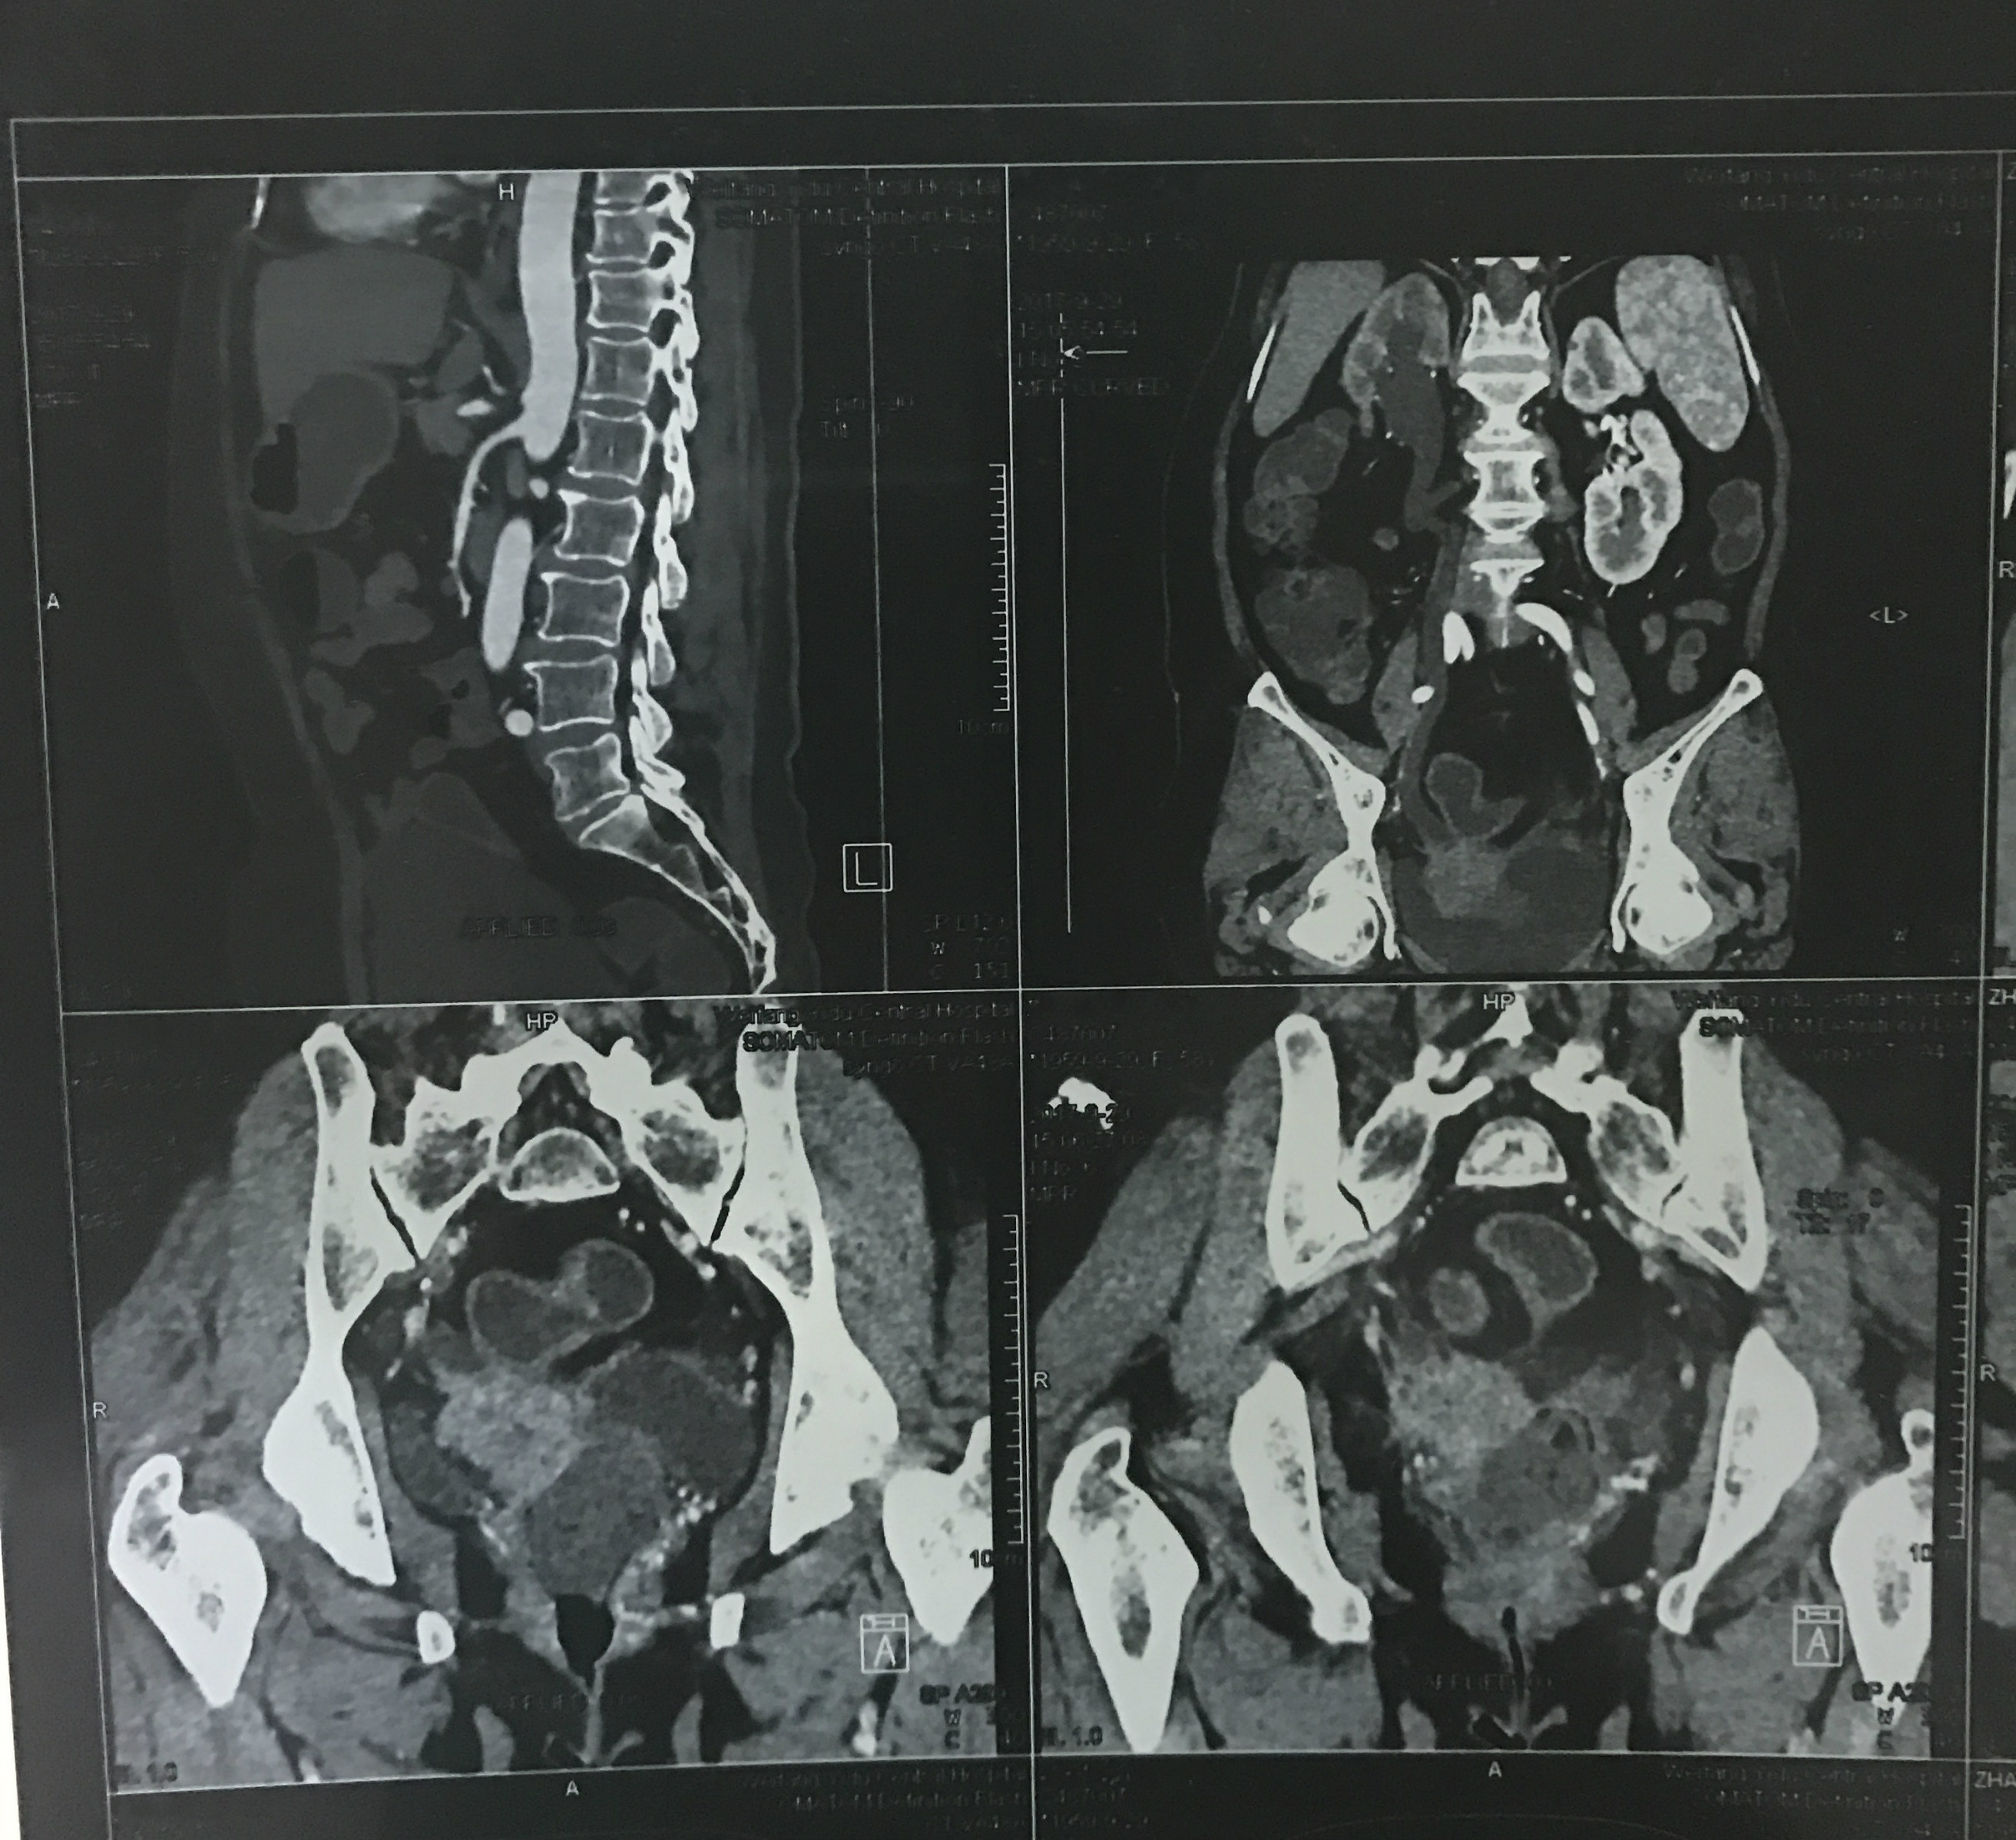

患者为一名老年女性,两年前因子宫颈癌行子宫全切术,近日肿瘤复发,入院后系统检查发现盆腔转移并侵犯临近组织,累及膀胱、右侧输尿管及直肠,右肾及输尿管积水。盆腔重要血管及脏器关系复杂、操作空间狭小,极大地增加了手术难度。

患者术前盆腔CT图